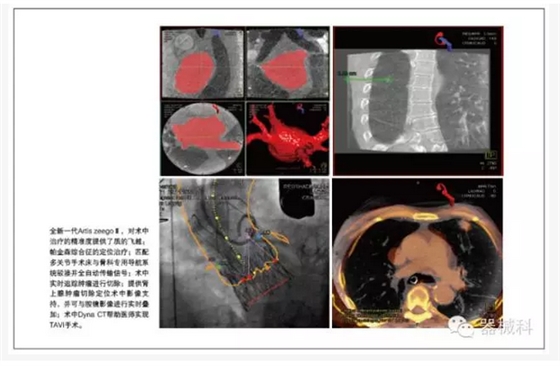

胸心外科是復(fù)合手術(shù)室的最重要使用科室之一。西門子在中國,在世界,都是心臟復(fù)合手術(shù)室技術(shù)的開創(chuàng)者和領(lǐng)先保持者。國內(nèi)著名的心血管病中心一直采用西門子復(fù)合手術(shù)室,并開創(chuàng)了心臟外科復(fù)合手術(shù)的“中國式經(jīng)驗”。在TAVI等治療上,西門子擁有獨特的軟硬件支持,特別是術(shù)中Dyna CT,可以幫助醫(yī)師實現(xiàn)TAVI手術(shù)。

在骨科領(lǐng)域,Artis zeego與傳統(tǒng)小C臂相比,劑量低,影像更清晰,并可提供特殊體位的3維重建和清晰的CT影像,巨大的投照面積,可提供全髖,肩關(guān)節(jié),全胸椎,全腰椎的一次成像,機器人提供的靈活投照角度,且具備投照記憶功能,大幅減少了術(shù)中劑量,縮短了手術(shù)時間;而且機器人可匹配多關(guān)節(jié)手術(shù)床與骨科專用導(dǎo)航系統(tǒng)駁接并全自動傳輸信號。

特別是術(shù)中實時的CT評估,對于術(shù)中治療的精準度提供了質(zhì)的飛越。其實,對于全新一代Artis zeegoⅢ,他的神奇還包括6秒360度極速旋轉(zhuǎn)采集,十字繡激光定位引導(dǎo)穿刺,多臟器的iFlow血流編碼及PBV功能成像。以及我們和內(nèi)鏡微創(chuàng)界的達芬奇機器人強強聯(lián)合,開展更尖端復(fù)雜的精準微創(chuàng)手術(shù)。